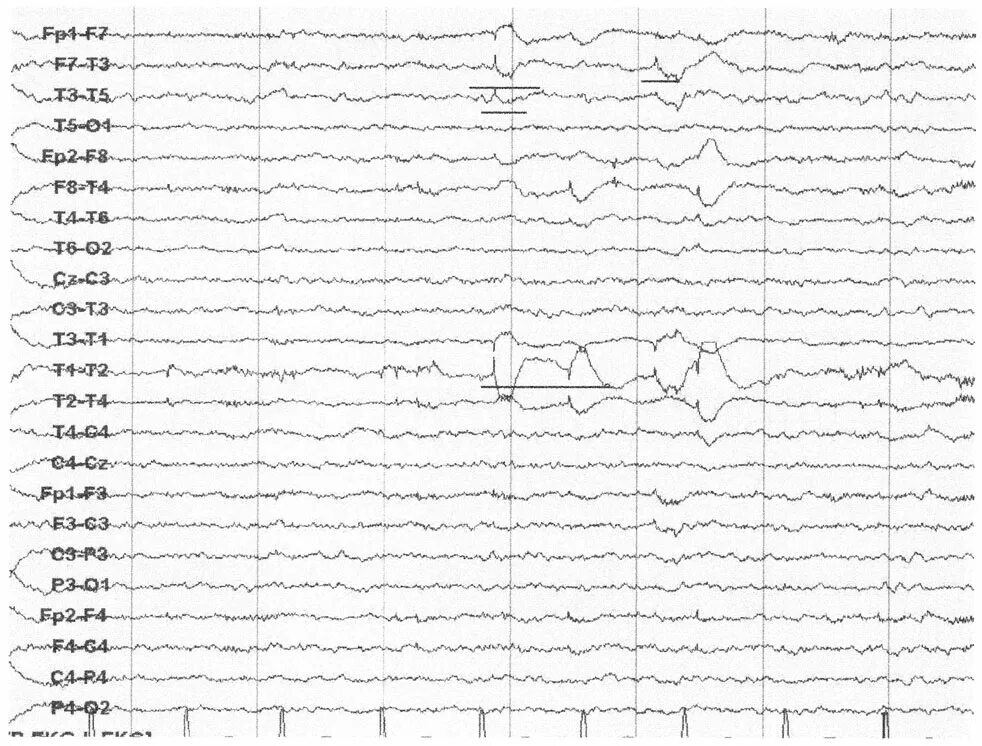

Ээг альфа